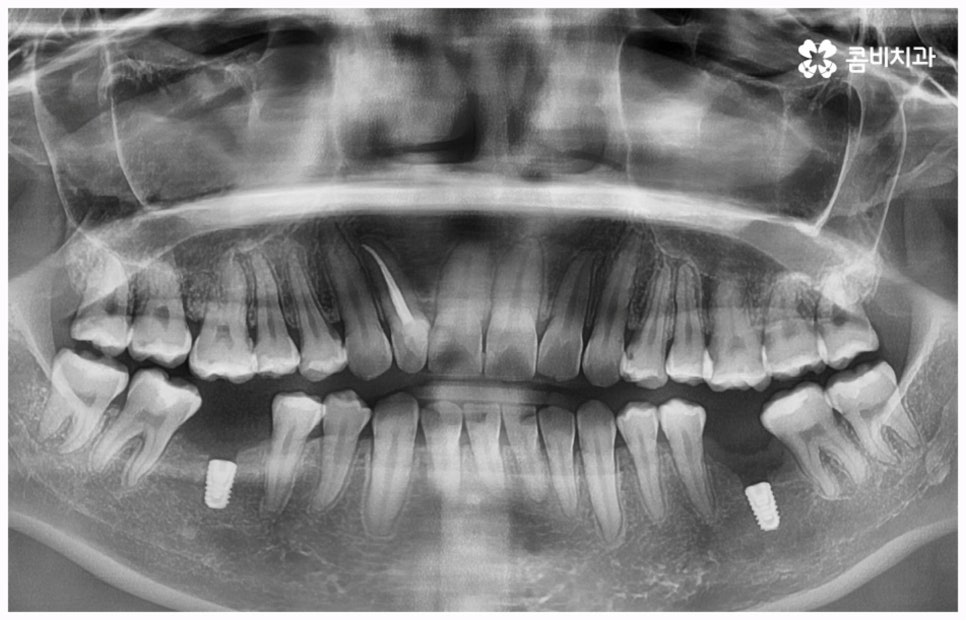

또한 임플란트 종류 중에 네비게이션임플란트라고 해서 3D-CT, 3D 컴퓨터 분석을 통하여 최적의 위치와 각도를 계산하여 정확하고 정밀하게 임플란트를 식립하는 방법이 있는데, 이와 같이 3D 모의 수술을 통해 제작된 가이드로 수술을 진행하게 되면 일반적인 경우 무절개, 필요한 경우 최소 절개를 하므로 통증이 적고 비교적 시술 시간이 짧아지며 상대적으로 출혈, 감염 등의 위험성을 줄일 수 있으니 전신 질환자 및 고령 환자분들의 경우 이 방법에 대해서도 고려해 보시고 상담을 통해 가능 여부를 알아보시길 권유드리고 있어요. 환자분들의 상황에 따라 개방 후 수술을 진행하는 것이 식립 성공률과 지속적인 안정성을 높이는데 유리하다는 판단이 들면 네비게이션 방법이 아닌 일반 임플란트 수술을 진행할 필요가 있기 때문에, 첨단 장비를 보유하고 풍부한 노하우를 통해 각 환자분들께 딱 맞는 치료 계획을 세울 수 있는 의료진과 충분하게 상담해 보시는 게 좋을 거예요.

임플란트는 관리를 철저하게 해 준다면 거의 반영구적으로 쓸 수 있다고 알려져 있을 만큼 잘 유지 관리하는 것이 굉장히 중요한데, 그 첫 단계가 정확한 위치와 각도로 식립하는 과정이라고 할 수 있어요. 임플란트가 잘못된 위치에 식립되거나 너무 깊게 또는 얕게 식립되면 교합이 잘 맞지 않고 저작 활동을 할 때 무리가 가 잇몸병을 유발함으로써 임플란트의 수명을 줄일 수 있기 때문인데, 이때 임플란트 제작시 커스텀 지대주를 사용하면 환자분들의 구강 구조에 정확하게 맞는 각도로 보철물을 식립할 수 있어서 더욱 편안한 사용을 할 수 있을 거예요. 식립 후 너무 많이 딱딱하거나 끈끈한 음식은 조심하시는 편이 좋으며, 이후 꾸준하고 지속적인 검진 및 스케일링 치료를 통해 위생을 청결하게 해 주면 임플란트 수명을 연장하는데 도움이 될 수 있습니다.